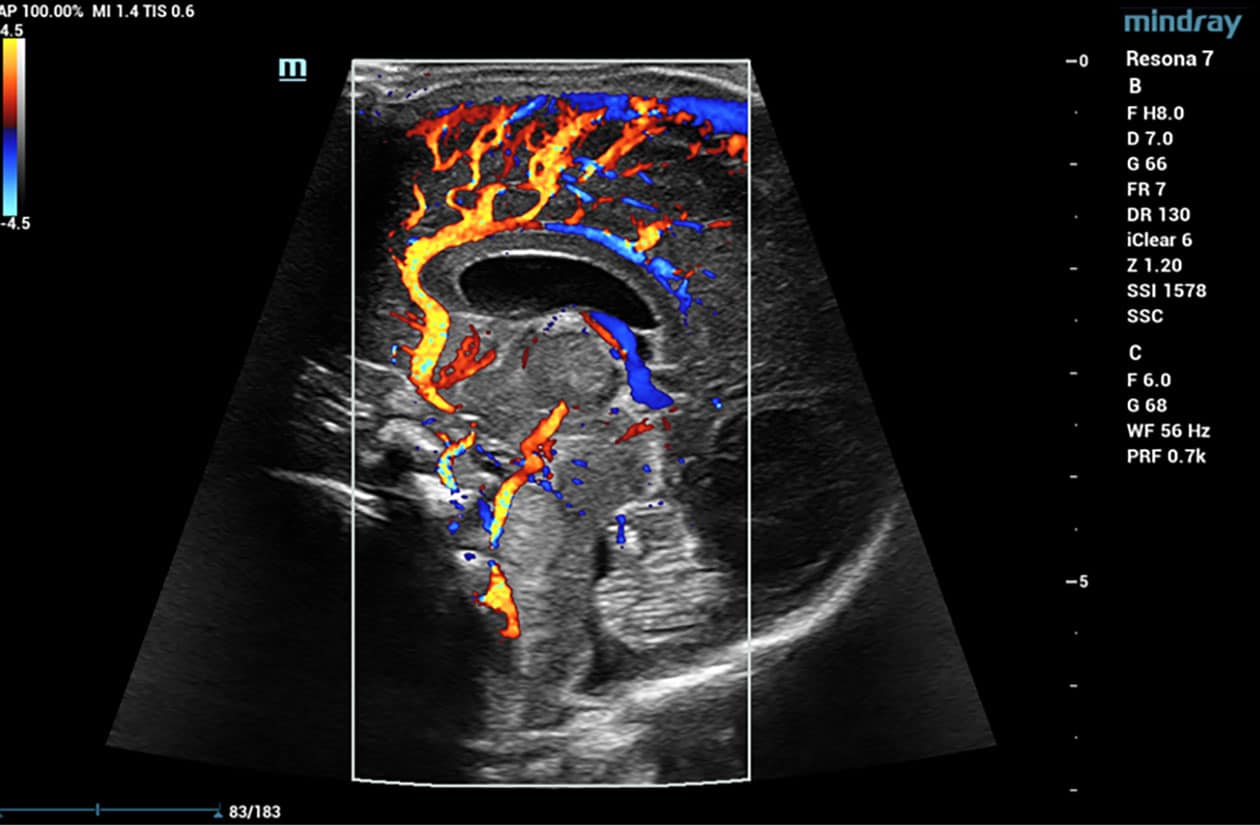

V Flow

V Flow imaging creates a quantitative map of hemodynamic states by tracking the acoustic speckle produced by microstreams of red blood cells as they flow through several non-temporally coherent transmit plane waves. The resulting information is plotted as arrows of varying lengths and colors expressing direction and velocity of blood within the interrogated area.